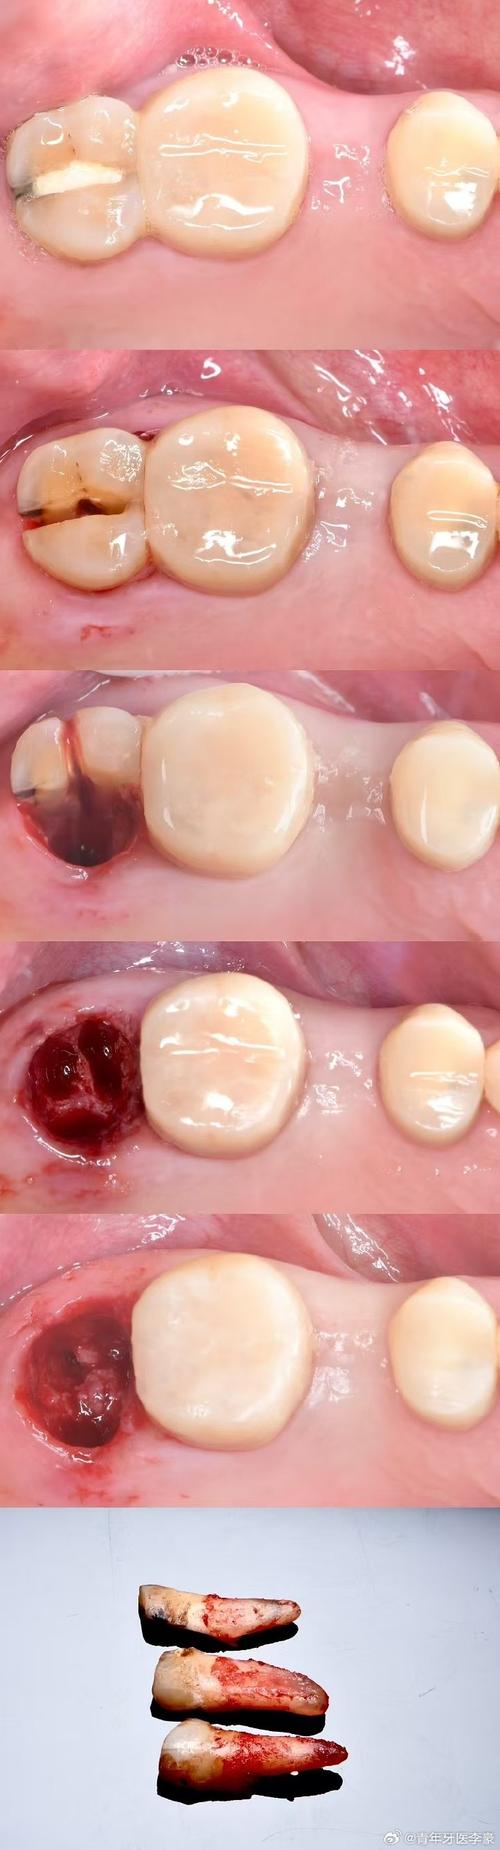

种牙前的磨牙通常指对牙槽骨的修整,当患者因长期缺牙、牙周病或外伤导致牙槽骨出现吸收、骨突或形态不规则时,种植体难以理想植入,此时需通过磨骨(骨修整)改善骨条件,术前医生会借助CBCT(锥形束CT)获取口腔三维影像,通过图片可清晰观察到牙槽骨的厚度、高度及神经管位置,若存在骨量不足或尖锐骨突,需设计磨骨方案,CBCT图片中可见牙槽嵴顶有明显倒凹,或邻牙牙根靠近缺牙区导致骨量不足,此时术中需用高速手机或超声骨刀去除多余骨质,修整出平整的骨面,为种植体提供“扎根”的理想空间,这一过程的图片可记录磨骨前后的骨形态变化,直观展示骨修整的效果。

磨牙操作的精准性直接影响种植牙的成功率,因此医生需严格遵循“少量多次”原则,过度磨除骨组织或牙冠会影响长期效果,术前通过影像学图片评估骨条件,术中实时监控磨骨深度,术后通过咬合图片验证调磨效果,是确保磨牙安全有效的关键,患者可通过这些图片直观了解治疗进展,缓解对未知操作的焦虑。